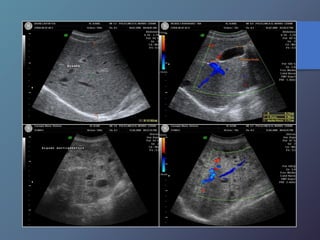

Anomalías Vasculares

• Presión normal de la porta: 5-10mmhg (14cm de agua).

• Se define como presión directa de la vena porta superior a

10mmhg.

• Puede dividirse en pre sinusoidal cuya causa mas frecuente

es la trombosis de la vena porta o esplénica.

• La cirrosis es la causa mas frecuente de hipertensión portal

intrahepatica.

• Características ecográficas: signos secundarios de

esplenomegalia, ascitis, colaterales venosas porto sistémicas.

• Se produce un aumento igual o mayor a 1.3cm.

Hipertensión Portal:

Trombosis de Lav Ena Porta

• Asociadas a neoplasias malignas como el chc, metástasis

hepáticas, carcinoma de páncreas y leiomiosarcoma.

• Otras causas: Pancreatitis crónica, hepatitis, septicemia,

traumatismos, esplenectomías y estados de

hipercoagulabilidad.

• Características ecográficas: Trombo ecógeno dentro de la

luz de la vena, expansión del calibre de la vena.

• Presencia de numerosos vasos a nivel del hilio hepático,

representando circulación colateral.

• El trombo agudo es anecoico por lo tanto debe realizarse

un estudio Doppler.